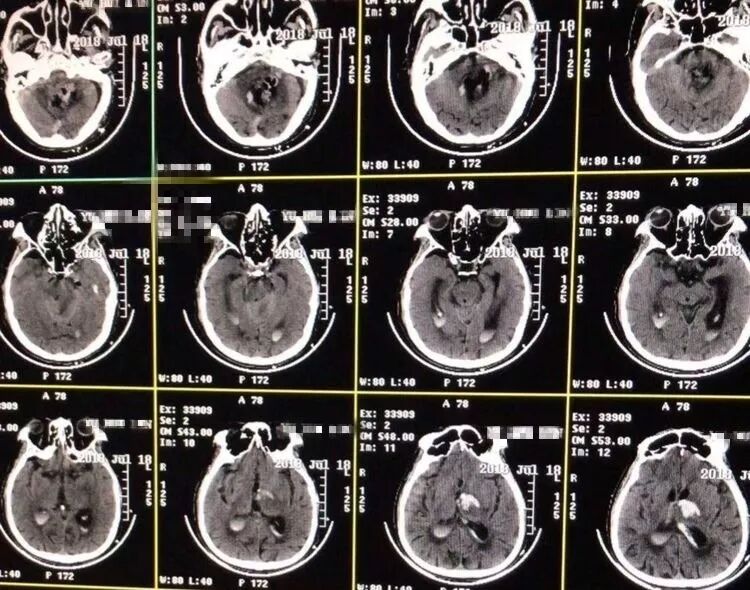

突发头痛2小时入院。既往高血压病史多年。入院后意识障碍逐渐加深,自主呼吸,节律不整齐,瞳孔正常大小。CT显示小脑蚓深部大量脑内血肿,IV脑室积血塑形,III脑室及侧脑室内积血。

术后病人意识水平明显改善,刺激睁眼,双侧肢体自主活动。复查头CT显示小脑血肿清除满意。

突发头痛,意识不清1小时。既往高血压病史多年,未系统治疗。自主呼吸深大,瞳孔正常大小。CT显示小脑蚓深部大量脑内血肿,IV脑室受压移位,III脑室及侧脑室内积血,左侧丘脑少量出血。

术后病人意识水平明显改善,刺激睁眼,双侧肢体自主活动。复查头CT显示小脑血肿清除满意,左侧丘脑内血肿未见增加,治疗中…